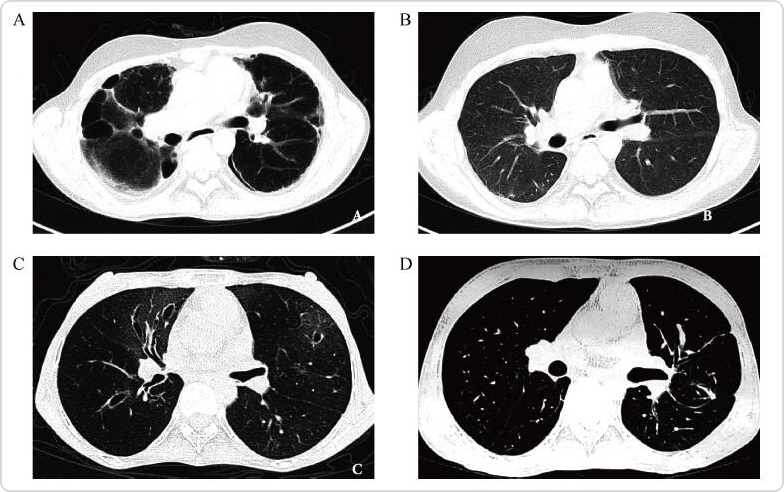

Lung transplantation is a treatment option for patients with end-stage BOS after HSCT. (A, B) One patient underwent bone marrow transplant for ALL in 2003 and he received BLT due to severe BOS in 2012. Since then, he has been leading a normal, active life. (C, D) Another patient suffered from BOS two years after HSCT, and she underwent BLT in 2014. Pulmonary function improved significantly after the transplant, and maintained normal during the follow-up. (Courtesy of Dr. Jingyu Chen. See pages 224-228 by Fei Gao et al. for more information.)